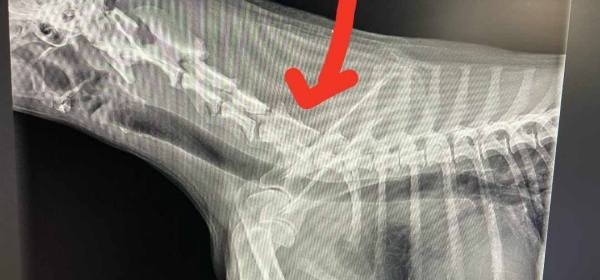

Bambusz befindet sich immer noch in der Tierklinik. Ihr Zustand ist schon wesentlich besser als vergangene Woche, dennoch ist weiterhin unklar wo das Problem liegt.